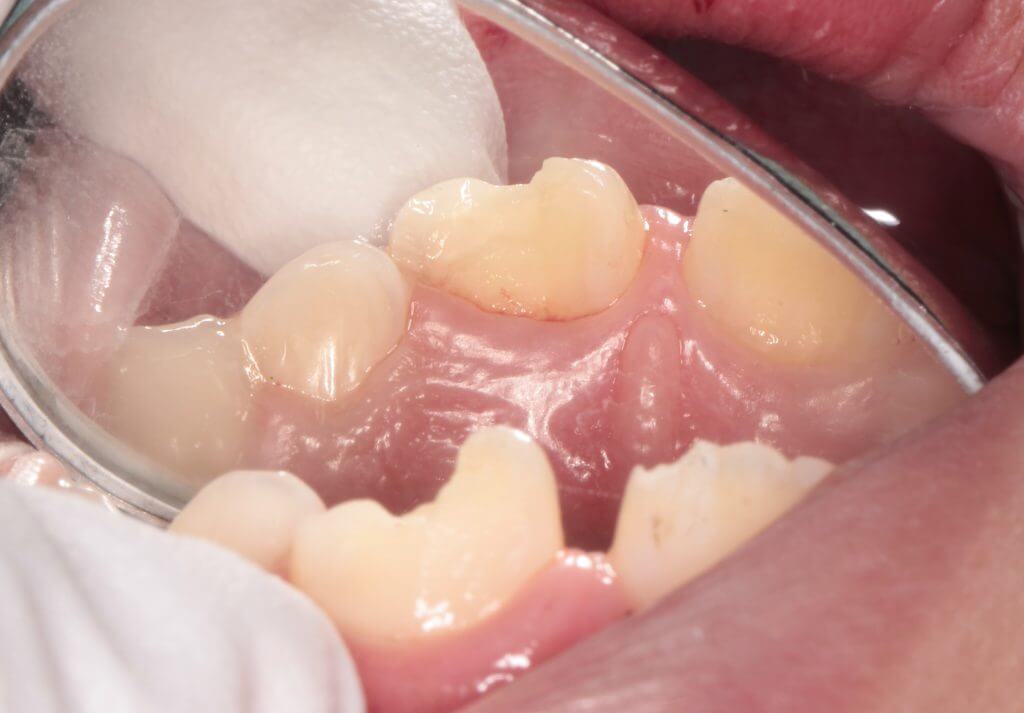

口腔内所見では露髄は認められず臨床症状もないため神経には問題はなさそうでした。レントゲン所見でも問題なかったので修復処置に移ります。今回は左側の大きく欠けた歯の一部をお母さんが探して持ってきていたので、それをコンポジットレジンで接着して修復の一部に再利用することとしました。